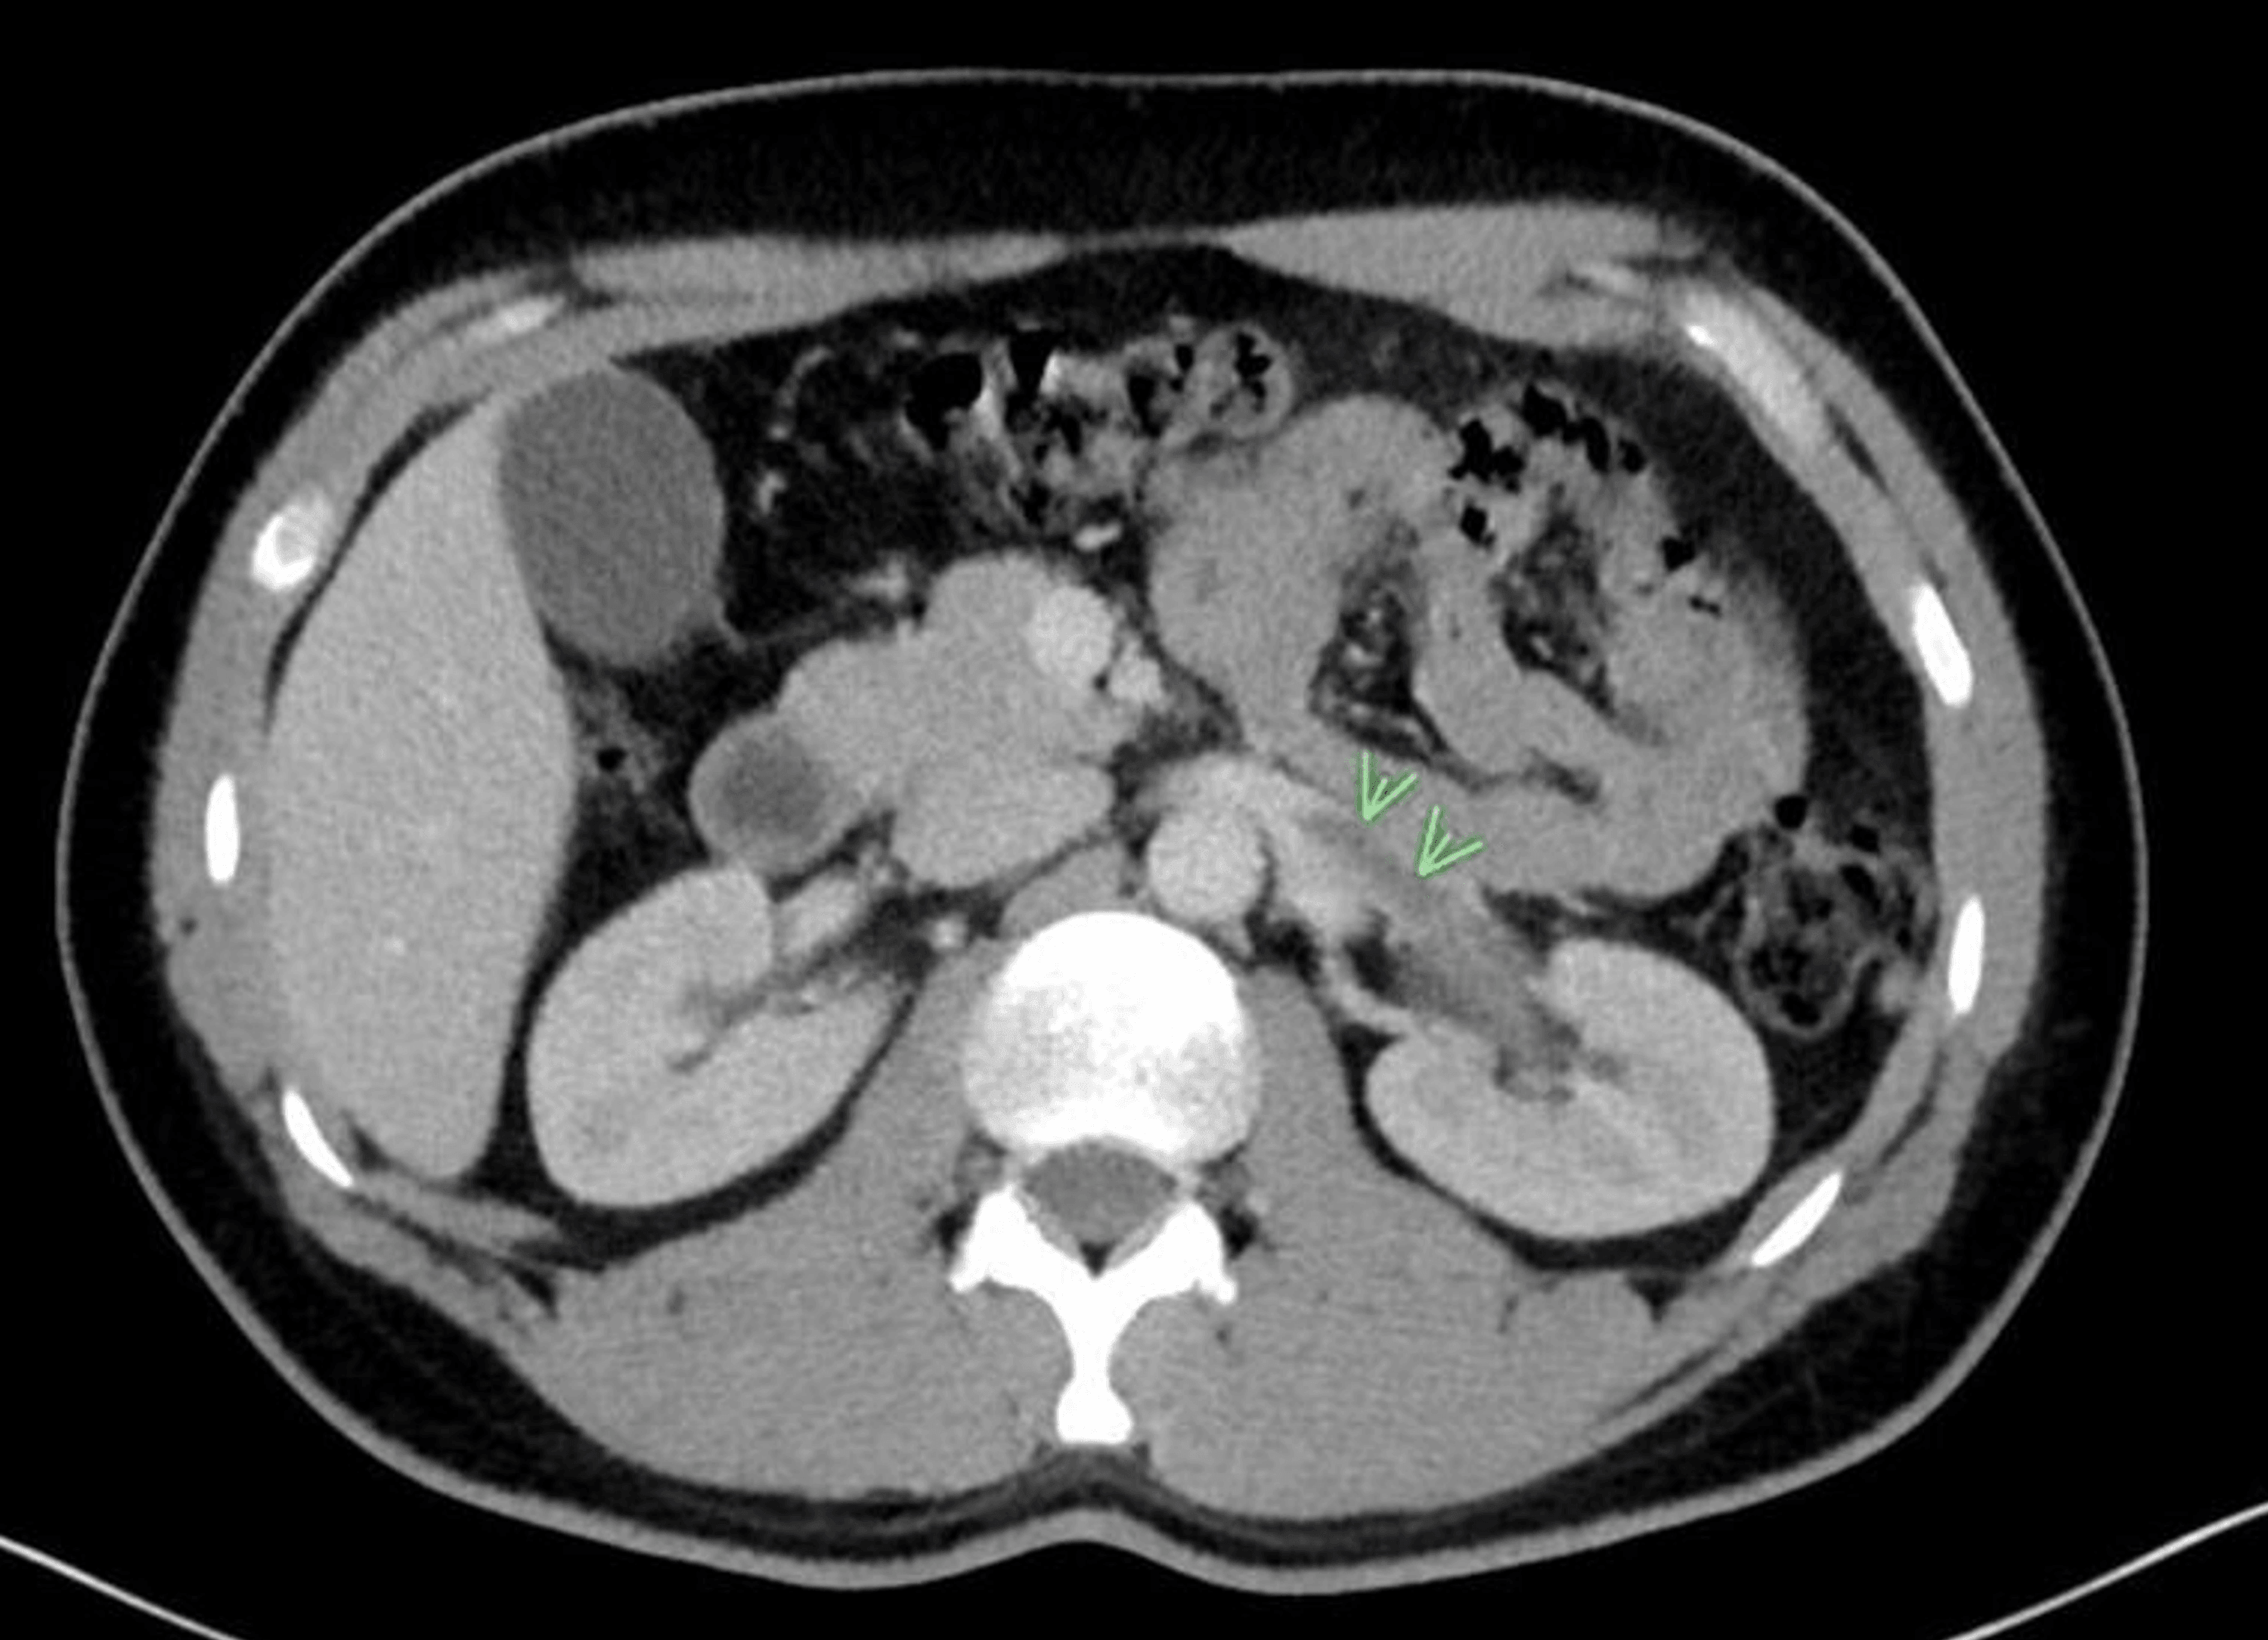

The presenting symptoms of acute renal vein thrombosis (rvt) can often be confused with. a rare case of a 35 years old woman presented with renal arcuate vein thrombosis (ravt) and acute kidney injury. here, we describe a case of acute onset flank pain caused by unilateral renal vein thrombosis (rvt) in a previously healthy patient. renal vein thrombosis (rvt), the presence of thrombus in the major renal veins or its tributaries, is a rare clinical entity.

Case Report On Renal Vein Thrombosis here, we describe a case of acute onset flank pain caused by unilateral renal vein thrombosis (rvt) in a previously healthy patient. a rare case of a 35 years old woman presented with renal arcuate vein thrombosis (ravt) and acute kidney injury. here, we describe a case of acute onset flank pain caused by unilateral renal vein thrombosis (rvt) in a previously healthy patient. The presenting symptoms of acute renal vein thrombosis (rvt) can often be confused with. renal vein thrombosis (rvt), the presence of thrombus in the major renal veins or its tributaries, is a rare clinical entity.